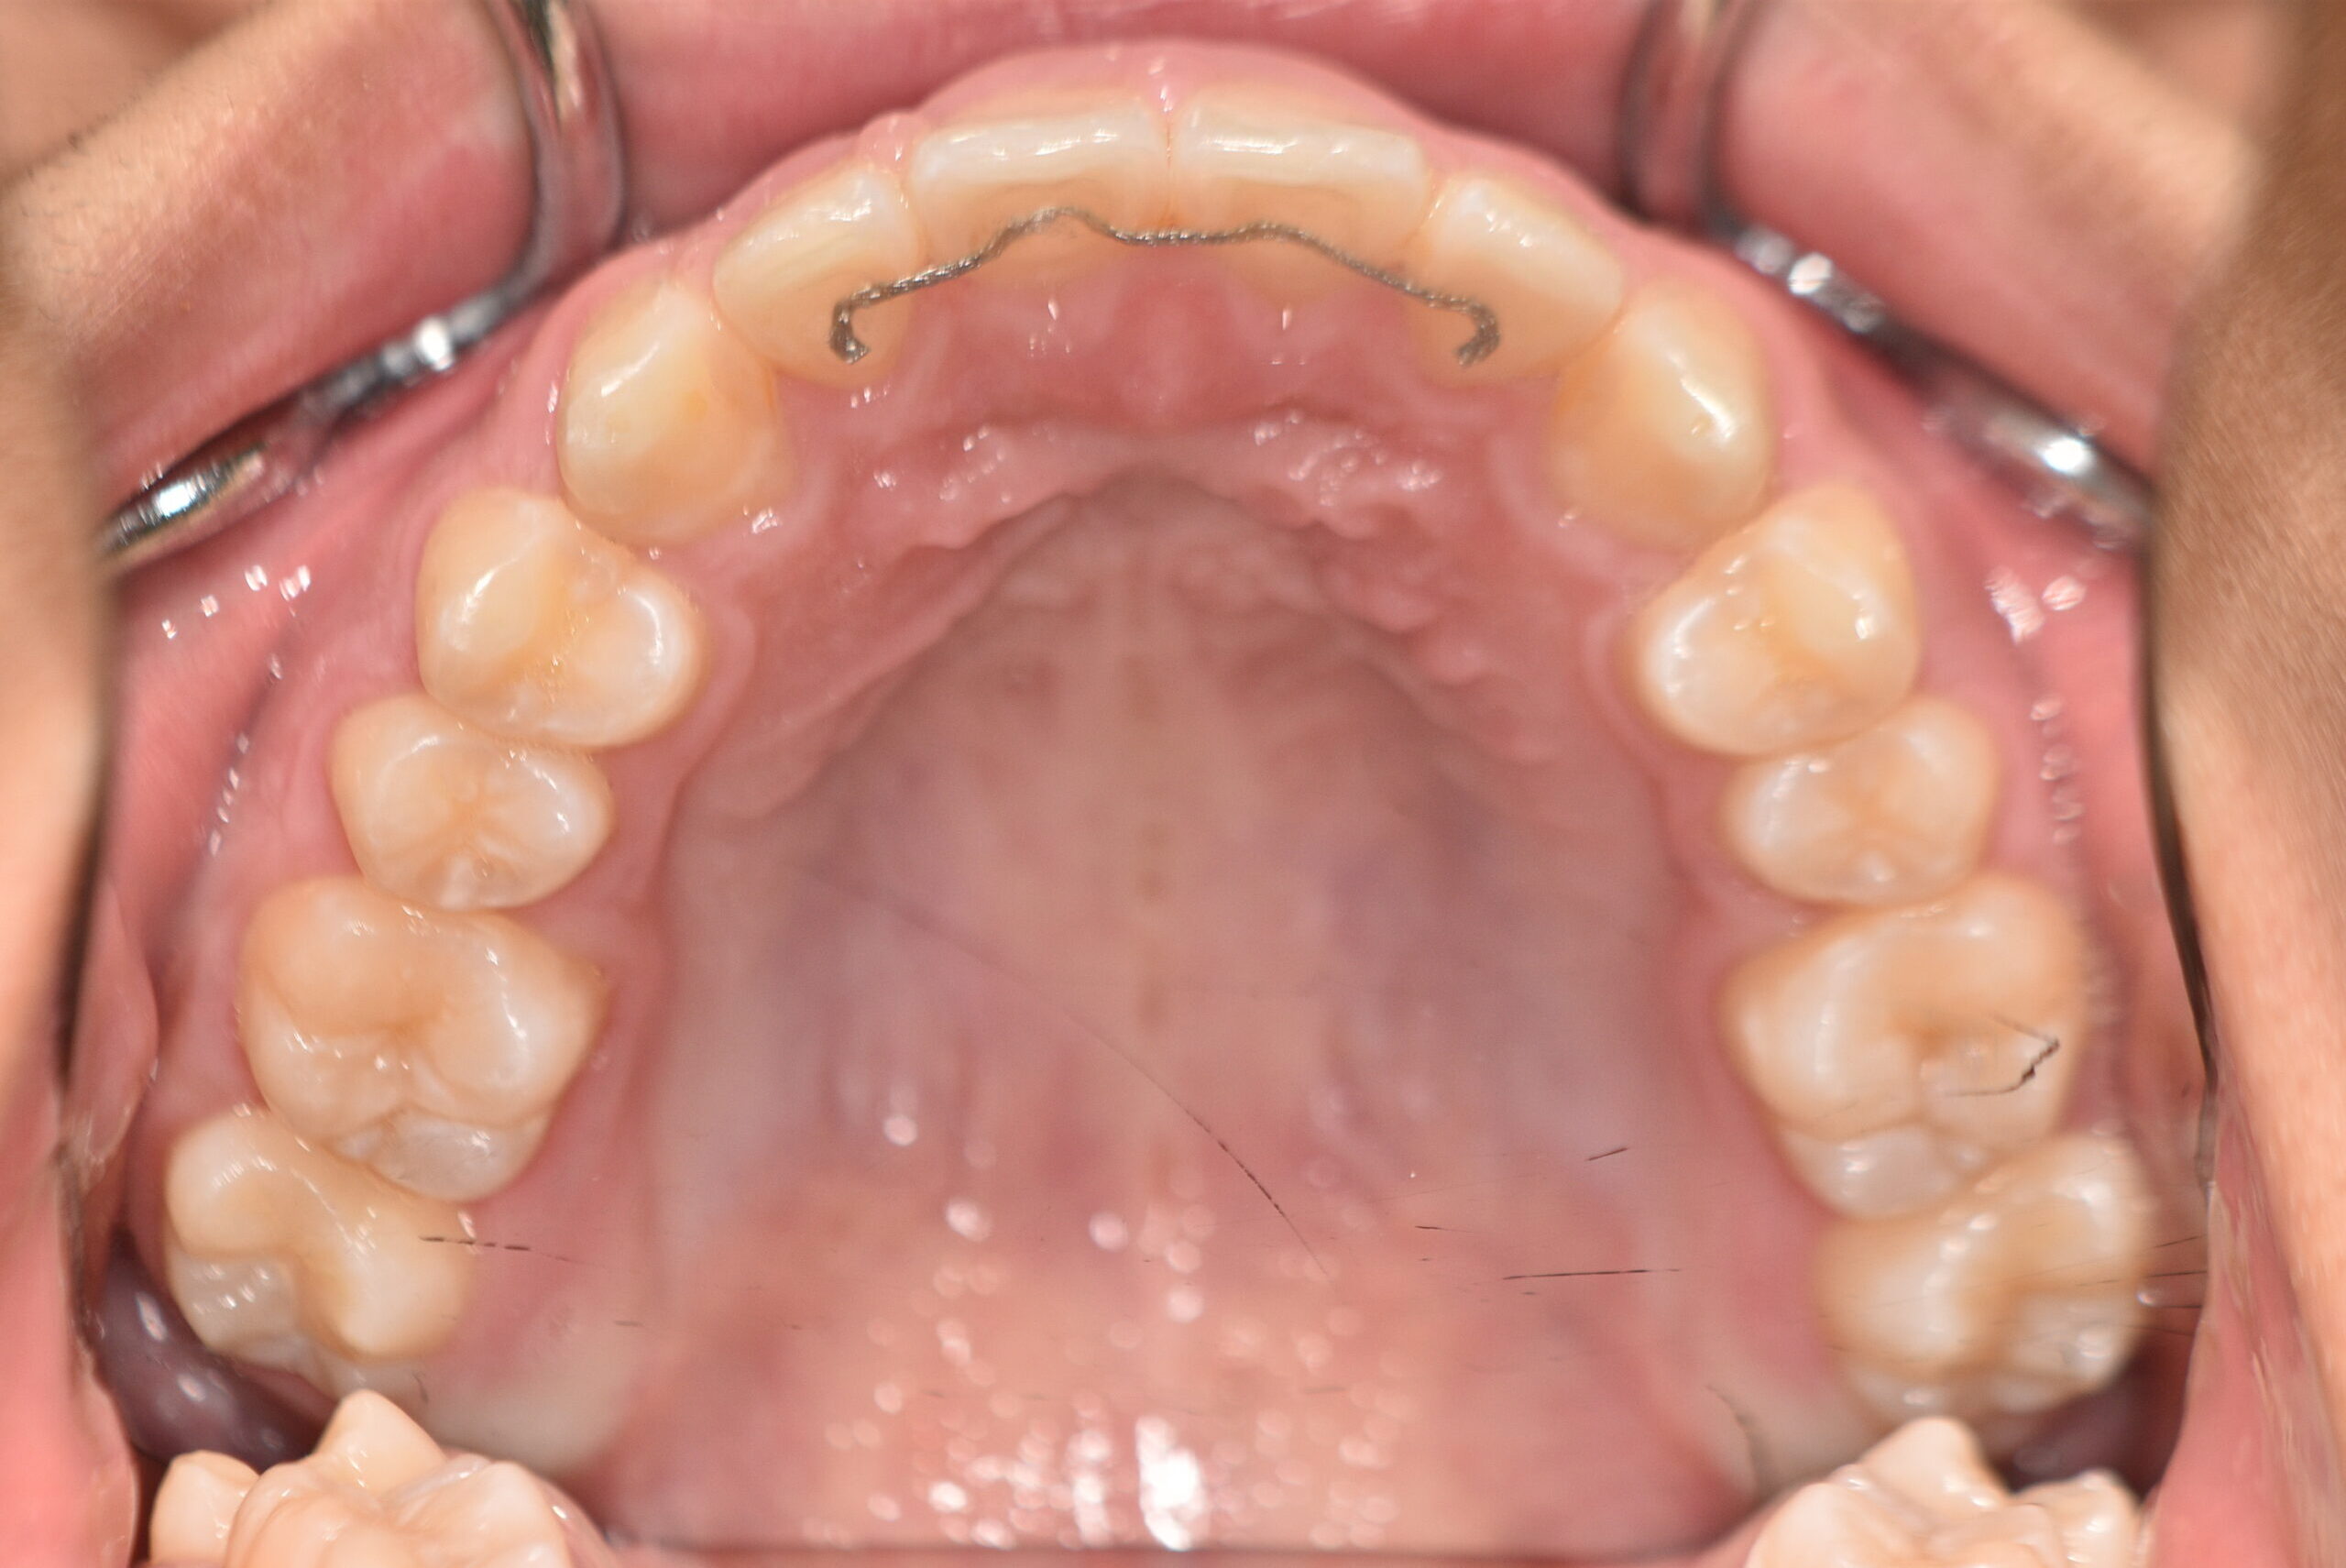

上顎前突(非抜歯)[2121]

動的治療終了時

症例 症例 症例 症例

治療内容の詳細 初診時8歳の男性で、癒合歯があり今後の歯並びが心配で来院されました。

検査の結果、過蓋咬合、上顎前突を伴うアングルⅡ級1類不正咬合と診断しました。

治療としては、初期段階の治療として、機能的矯正装置で鼻呼吸の獲得と舌の位置や口唇の閉鎖といった筋機能習癖の改善を行いました。

永久歯列に交換後、非抜歯の上、セルフライゲーションブラケット装置(デーモンシステム)で歯の配列と咬合関係の改善を行いました。

治療期間は、5年10ヶ月でした。